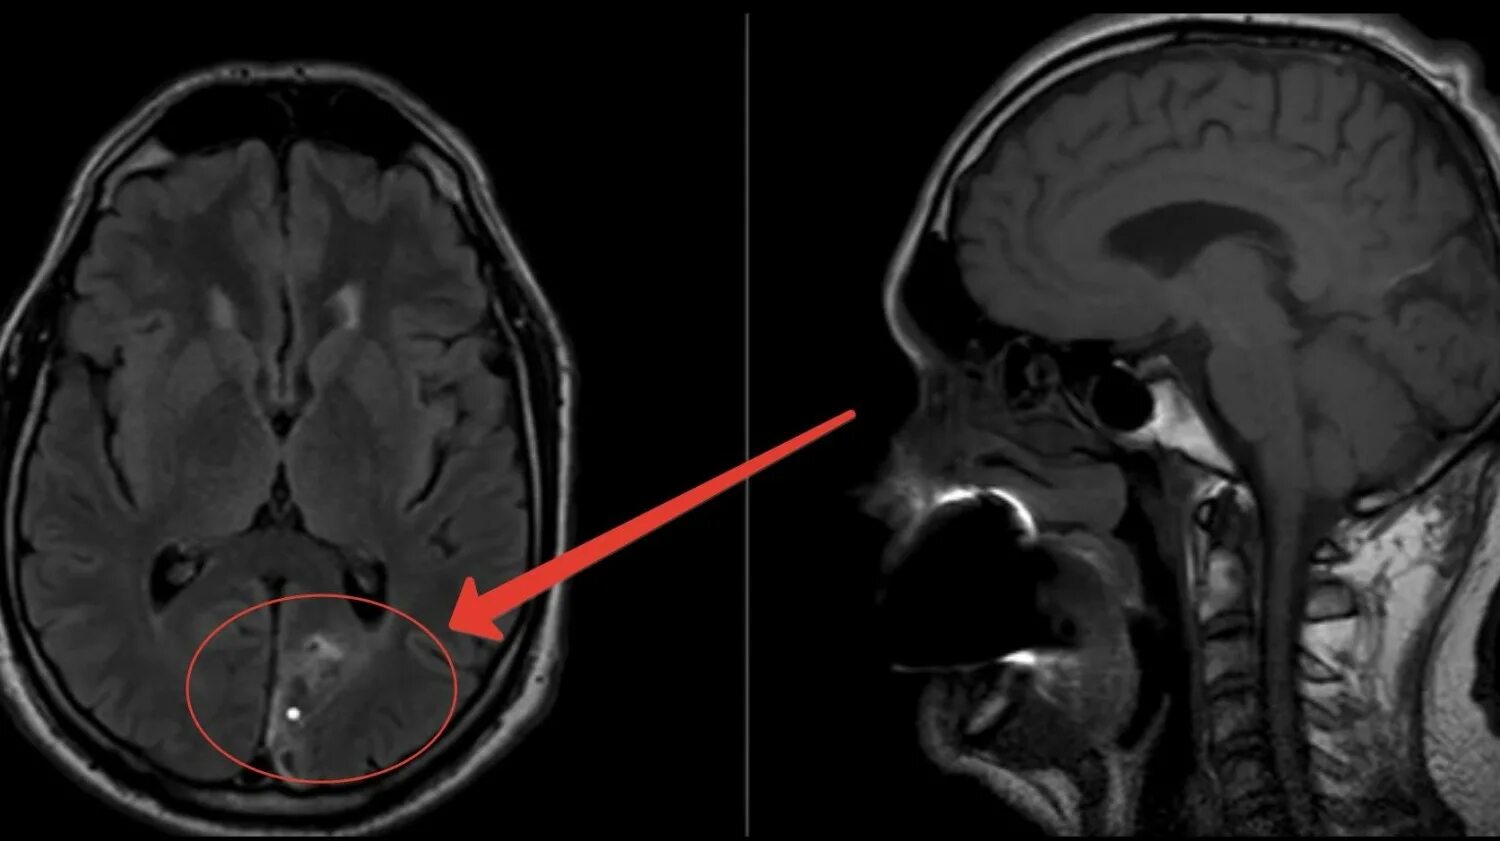

Что можно увидеть на мрт